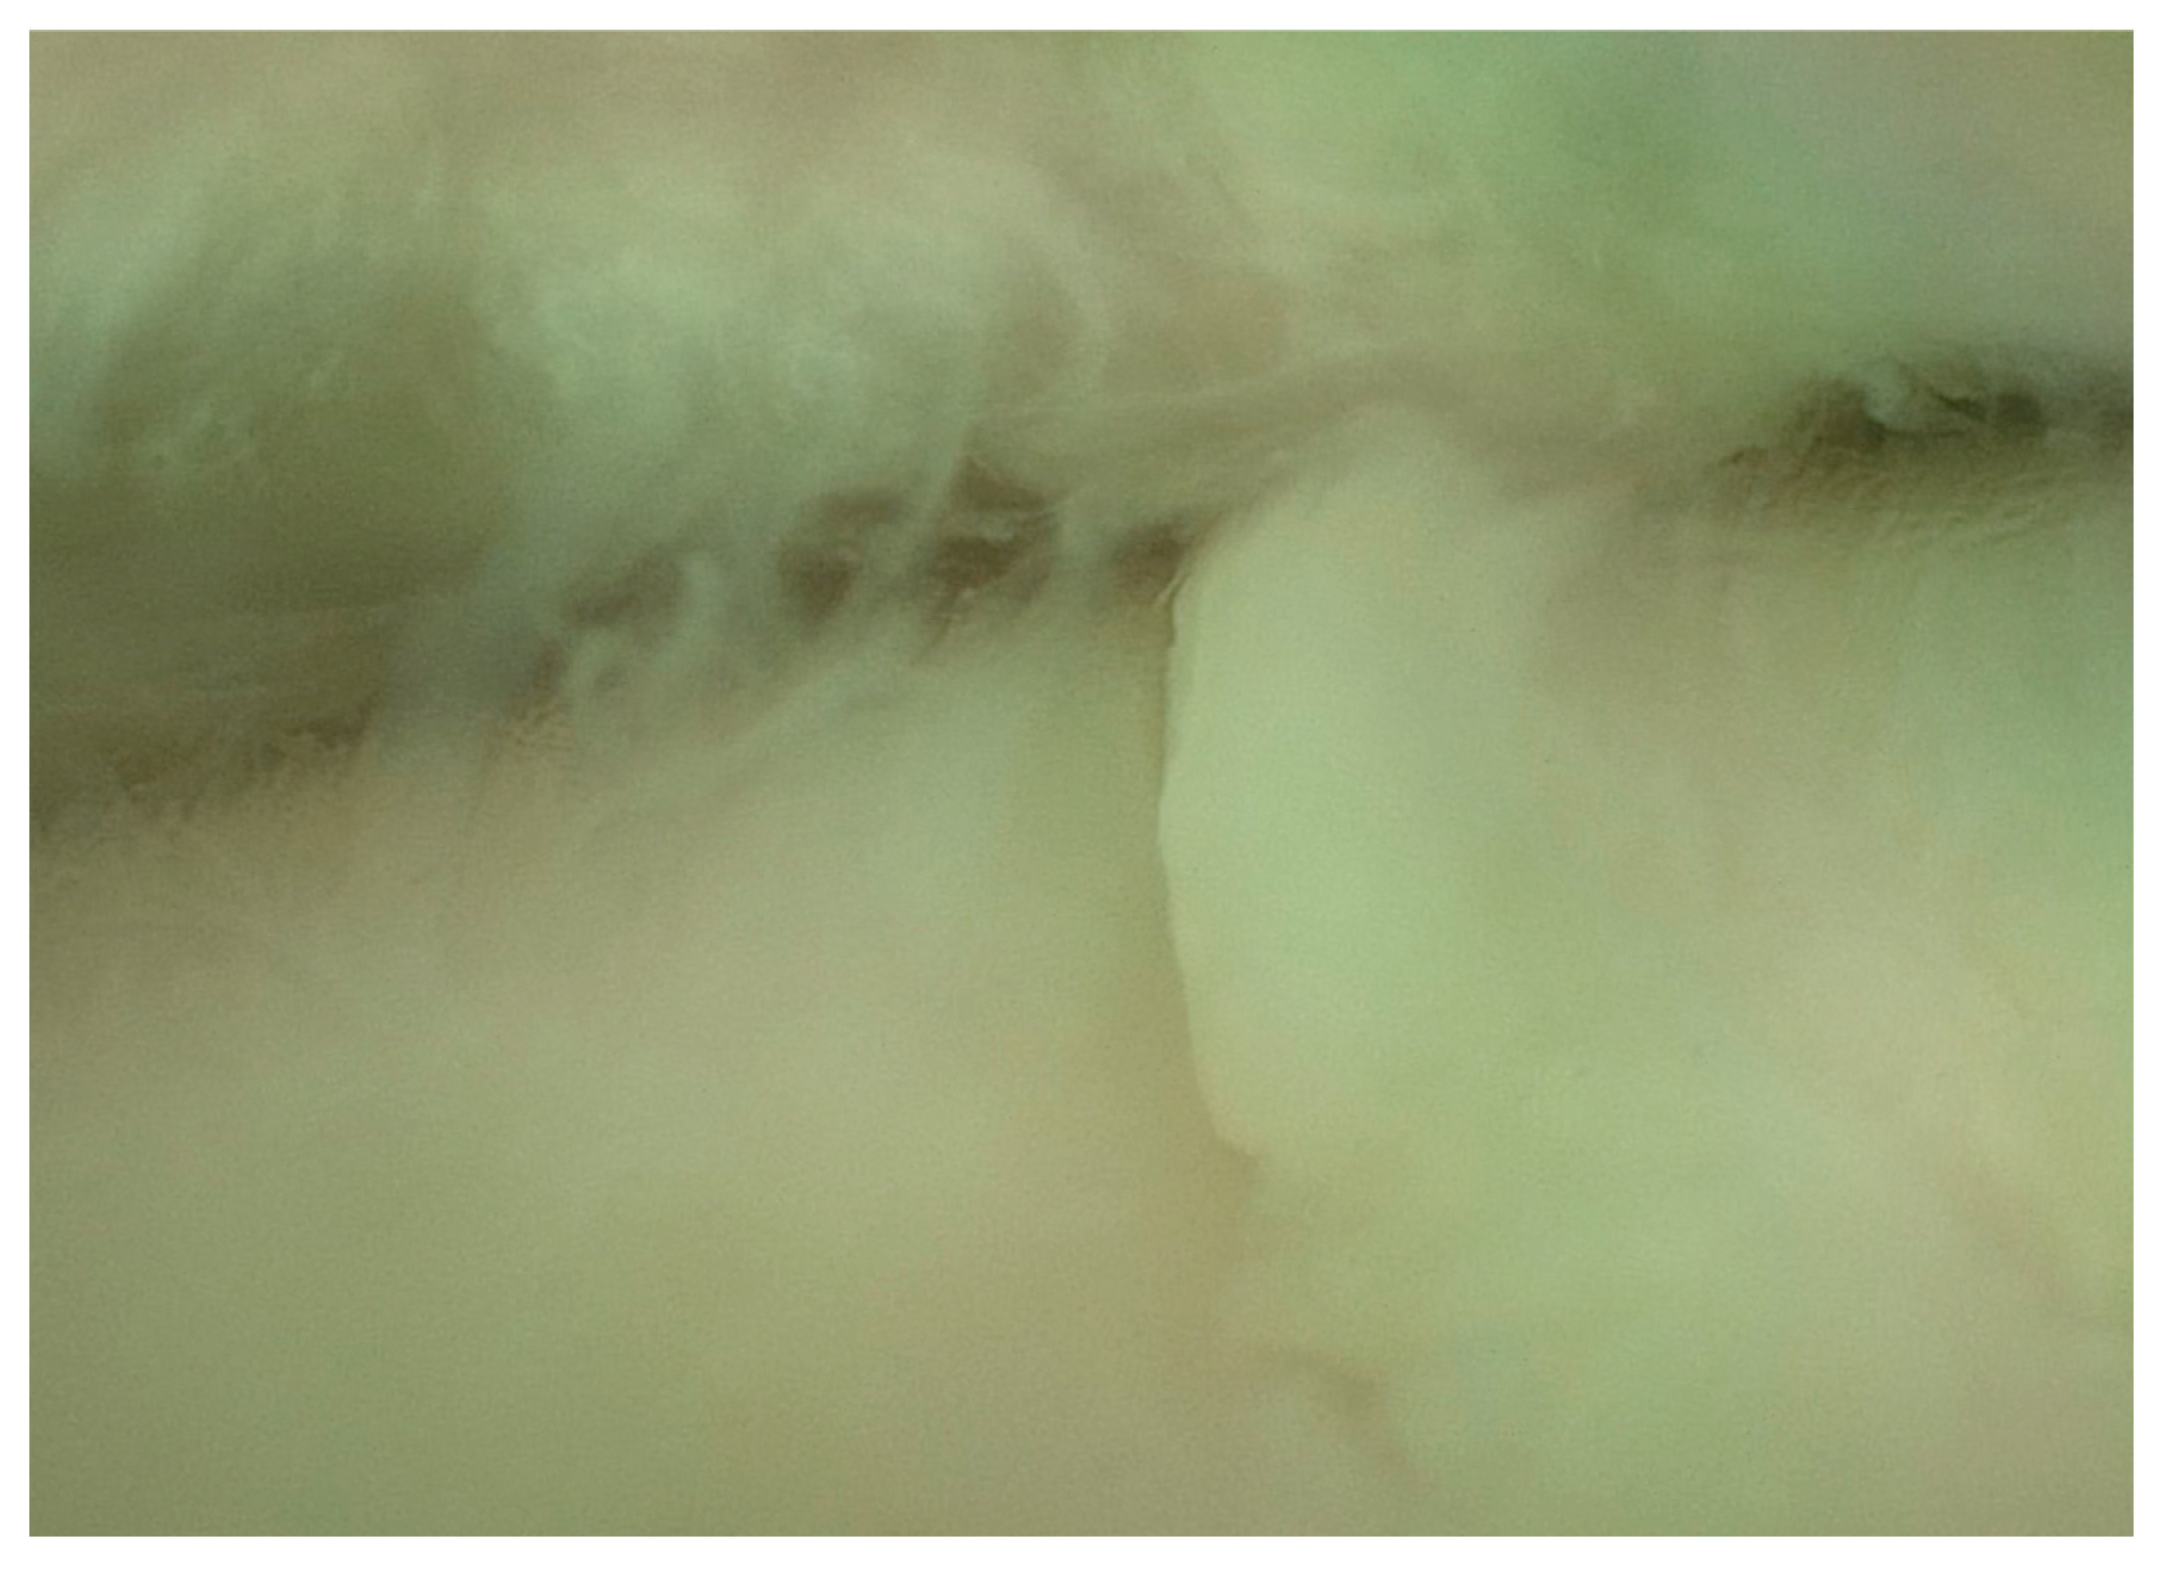

- Articular surface fibrillation (Figure 4)

- Partial erosion of the articular surface (Figure 5)